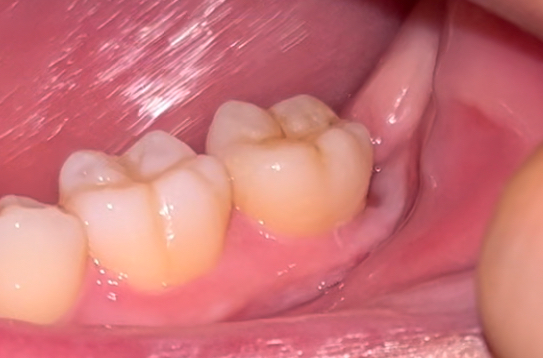

매복사랑니 발치 후 잘 아물은 걸까요?

안녕하세요 뿌리만 남겨놓은 매복사랑니 발치한지 한달이 되었습니다. 그림자인건지 아닌지는 잘 모르겠는데 아직 메꿔지지 않은 구멍이 있는 것 같아 보이기도 하고, 잇몸 짼 부위가 아직 색이 회색인 것 같아서 질문합니다.

잘 아물고 있는 걸까요? 혹시나 하는 마음에 밥 먹을 때 계속 반대편으로만 씹고 있습니다. 가끔가다 찌릿한 느낌이 들 때도 있습니다.

잘아물고 있는 것으로 보이며 식사도 편하게 하셔도 괜찮습니다. 양치만 잘해주면 됩니다.

매복사랑니 발치를 하신경우 잇몸 절개를 넓게 하셧고 잇몸뼈도 삭제를 햇기 떄문에 잇몸이 아무는데 시간이 좀 걸릴수 있습니다. 시간이 지나면 괜찮아 지실꺼에요.

잇몸 초기 치유는 어느정도 이뤄진 것 같습니다. 초기 치유는 1~2주 정도 걸리고요. 그 이후로도 2~3달 정도 잇몸이 완전히 치유되고 내부의 잇몸뼈가 차오르는 기간이 걸립니다. 잇몸 초기 치유 정도만 잘 지났다면 해당 부위로 너무 무리하지 않는 선에서 음식 드셔도 괜찮습니다.

현재 사진상으로는 잘아물고 있는 것으로 보이며, 비어있는 구멍은 시간이 지남에 따라 잇몸이 차오르게 됩니다.